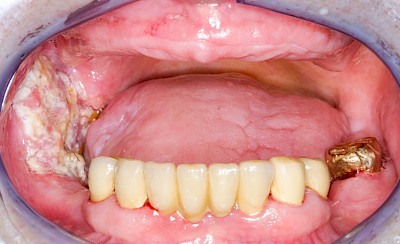

Schwellung ohne Eiter: faltenförmig

Als Sonderform des Reizfibroms können bei Zahnprothesen in den Randbereichen selten am Gaumen, häufiger außen in den Umschlagfalten in Ober- und Unterkiefer auch lappenartige Auffaltungen (Lappenfibrome) beobachtet werden, die ebenfalls aufgrund eines mechanischen Dauerreizes entstehen. Alle diese Veränderungen sind in der Regel eher wenig schmerzhaft – auch wenn man darauf drückt. Hier sollte zeitnah mit einem Zahnarzt eine Abklärung erfolgen.